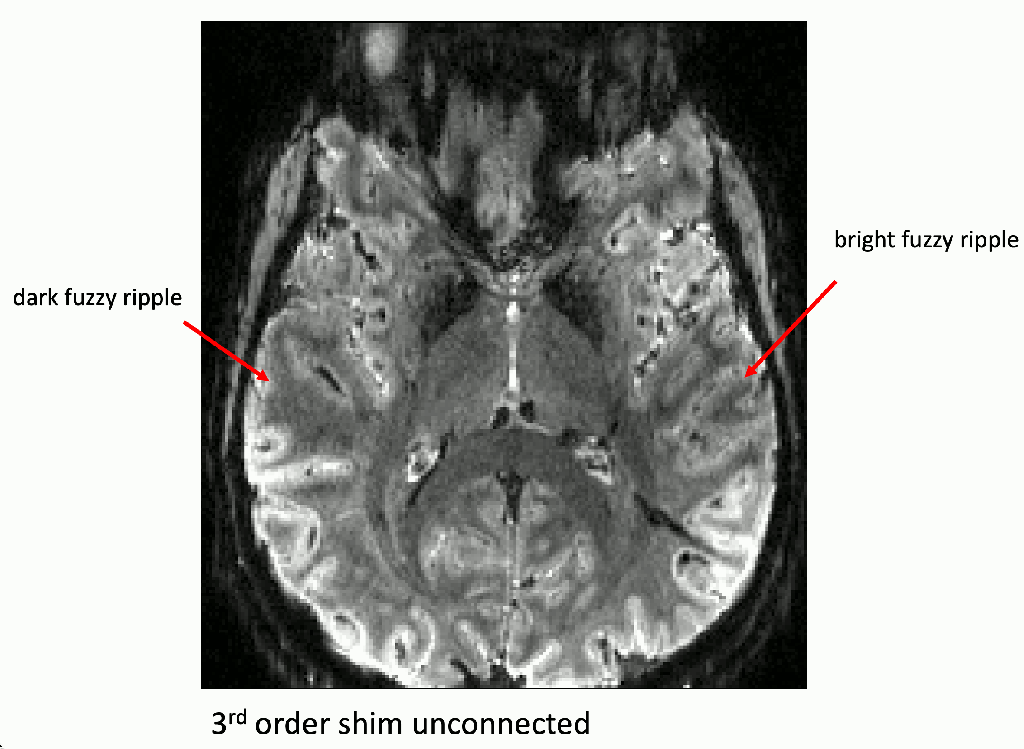

On Oct 13th 2023, Nicolas Boulant presented an intriguing source of MRI image artifacts at the CMRR high field meeting in Minnesota. He suggested that the 3rd-order shim can result in amplified gradient trajectory imperfections. In low bandwidth FLASH, this can manifest as faint ghosts in the read direction shifted by a few pixels. In EPI, on the other hand, these trajectory errors can result in fuzzy ripples (low spatial frequency ghosts and shadings, not edge ghosts).

In a recent meta analysis of all openly available layer-fMRI datasets, I had found had that the fuzzy ripples are one of the main limits of high-quality layer-fMRI acquisition (see here) across vendors. So, I was curious whether the 3rd order shim might be partly related to this. In this blog post, I am describing my attempts to reproduce Nicola’s results and investigate the effect of the 3rd order shim on layer-fMRI protocols. I find that disconnecting the 3rd order shim can result in significantly better data quality. However, this finding is only visible for specific echo-spacings, which are either in the ‘forbidden frequencies’ or which have side bands in the forbidden frequencies.